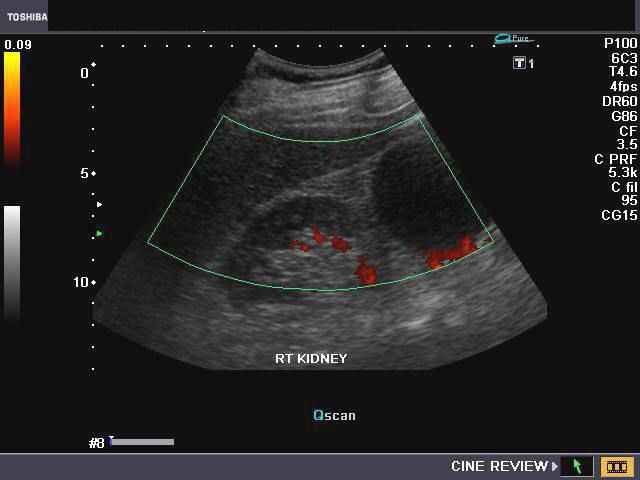

The left kidney in this male child shows a prominent column of renal cortex in the middle third of the kidney. This column of tissue is seen encroaching on the renal sinus, with the renal contour (outer margins of the left kidney) appearing normal. Color Doppler images of the left kidney show normal vascular pattern in the column. The echogenicity and echotexture of the column of tissue appears similar to the adjacent renal cortex. These ultrasound images and the sonographic findings are typical of what is called hypertrophied column of Bertin. The current terminology for this benign normal variant is junctional parenchyma. This new term for a long understood normal variant, is used as the renal tissue in the column of Bertin does not show any evidence of hypertrophy. The tissue in the junctional parenchyma/ hypertrophied column of Bertin is absolutely normal renal parenchyma and contains renal cortex, pyramids and septa or columns of Bertin. the renal tissue in the column is continuous and merges with the adjacent cortical tissue of the kidney. The column of Bertin is most commonly seen involving the left kidney as in the case above.